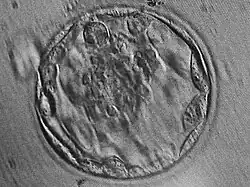

Бластоциста

Внешне бластоциста представляет собой шар, состоящий из нескольких десятков или сотен клеток. Размер бластоцисты колеблется от долей миллиметра (0,1 мм у грызунов и человека) до нескольких миллиметров (у непарнокопытных). Эмбрионы на стадии бластоцисты состоят из двух различных типов клеток: трофобласта (трофэктодермы) и эмбриобласта (внутренней клеточной массы)[1]. Трофобласт формирует внешний слой эмбриона — полый шар или пузырёк. Эмбриобласт формирует внутренний слой бластоцисты, располагается внутри трофобластатического пузырька в виде скопления клеток у одного из полюсов шара (внутренняя клеточная масса). Трофобласт участвует в имплантации (прикрепление эмбриона к эпителию матки, инвазия внутрь эндометрия матки, иммуносупрессорное действие, разрушение кровеносных сосудов), а также в формировании эктодермы ворсинок хориона (эктодермальная часть плаценты). Эмбриобласт даёт начало собственно телу плода, а также мезодермальным и энтодермальным структурам внезародышевых органов (желточному мешку, аллантоису, амниону, мезодермальной части хориона).